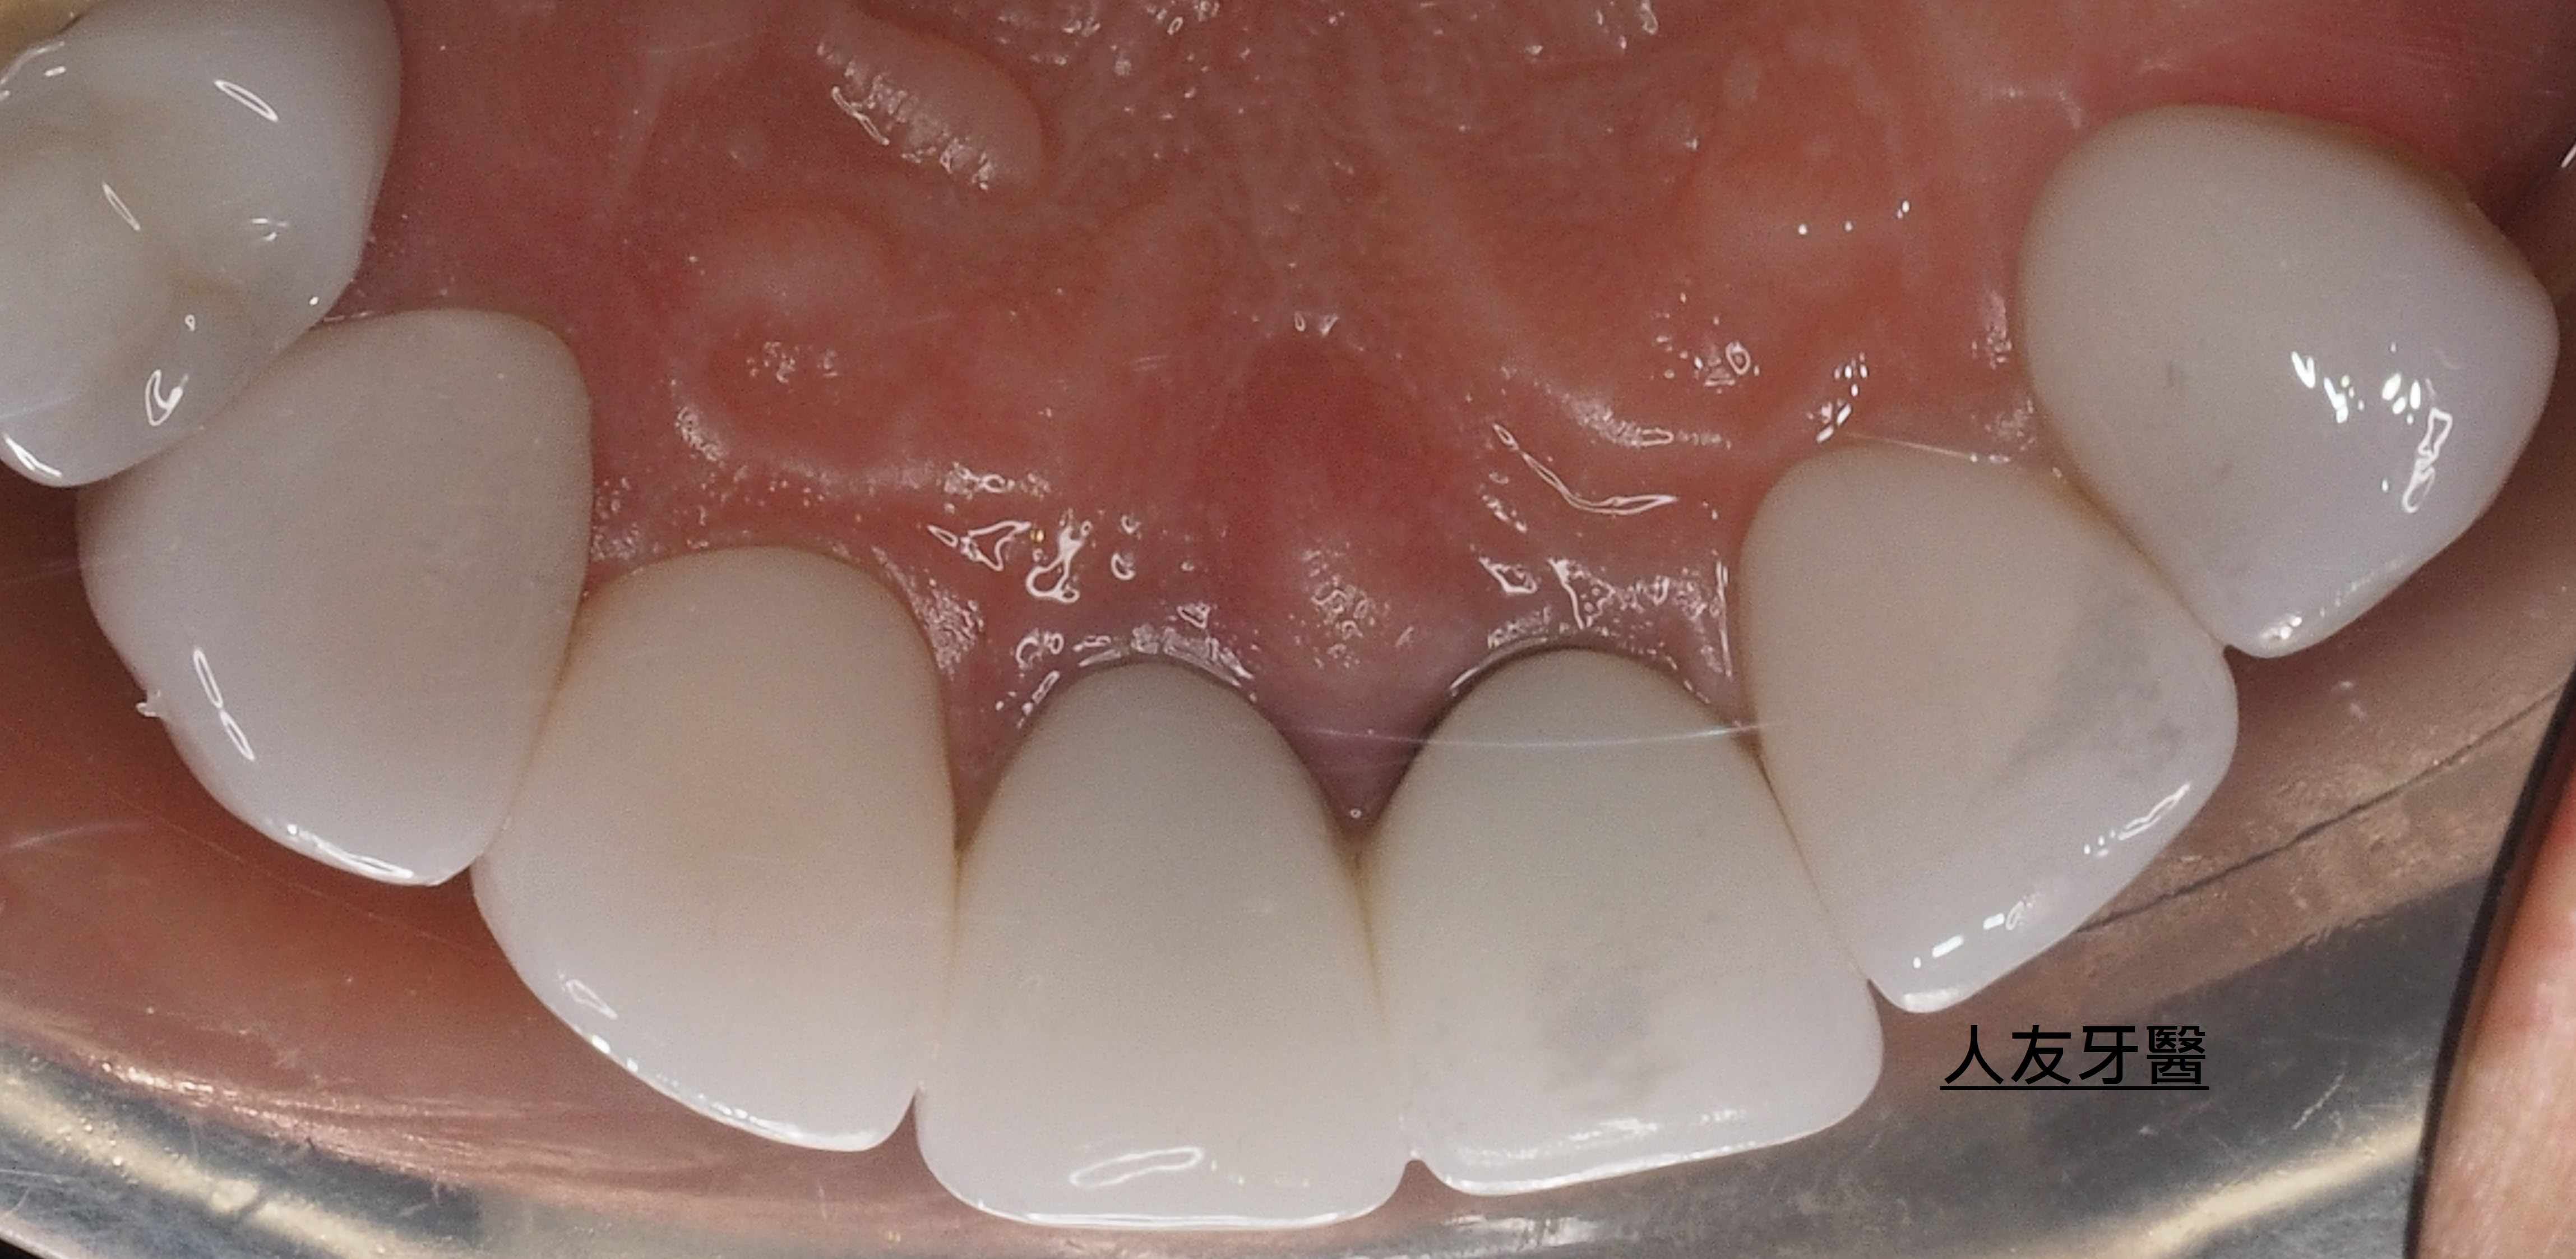

患者右上側門牙牙根不穩,牙齦萎縮導致黑邊明顯露出牙根(上圖),經由牙醫師建議更換氧化鋯牙套,也調整改變咬合及牙齒的長度,避免牙齒長期受到撞擊傷害。

為何選擇氧化鋯牙套原因如下:

1.自然透光不會有黑 邊困擾,幾乎與真牙無異(下方真牙照片右圖)。

2.高生物相容,不刺激牙齦不會變色,對牙齦友善。

3.3D電腦掃描設計擁有更精準的密合度,保護牙根並延長牙齒壽命。(下圖)

4.堅固耐磨,適用前牙及後牙(下右圖)。